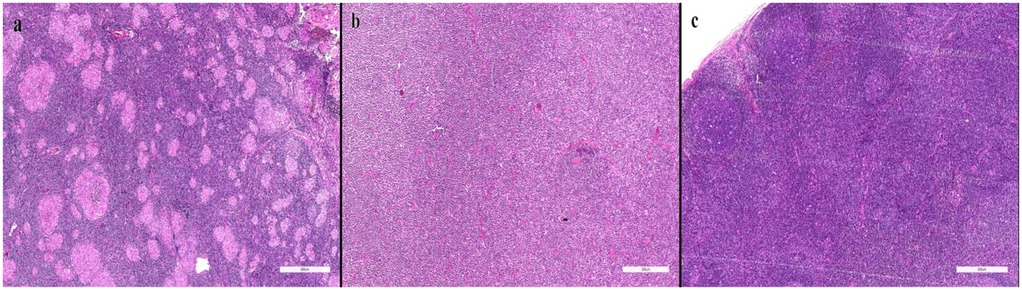

Pediatric lymphadenopathy is common, yet distinguishing benign from malignant causes remains challenging; objective predictors are needed to refine biopsy decisions. We retrospectively analyzed 500 children (0–18 years) with regional enlarged lymph nodes evaluated at a tertiary pediatric hematology–oncology clinic (June 2024–March 2025). Demographics, node location and size, multiplicity, ultrasonographic (US) assessment, viral tests, biopsy, and bone marrow results were extracted from the hospital system. Associations with definitive diagnosis were tested, and multivariable logistic regression identified independent predictors of malignancy. Median age was 6 years; cervical nodes were most frequent (92.2%), and multiple nodes were present in 93.6%. Biopsy was performed in 47 patients, yielding malignancy in 23 (48.9%). Final diagnoses were reactive lymphadenopathy (87.4%), hematologic malignancy (4.4%), and metastatic solid tumors (1.4%). On univariable analyses, larger size (≥2 cm), multiplicity, and certain regions were associated with malignancy (p<0.05). However, in multivariable analysis only US findings remained independently predictive: nodes categorized as suspicious on US were associated with an approximately 56-fold increase in the odds of malignancy (adjusted OR ≈55.6; 95% CI ≈14.3–200; p<0.001), whereas size and anatomical region were not significant. These data support an ultrasound-centered approach to biopsy referral in childhood lymphadenopathy, potentially reducing unnecessary invasive procedures while maintaining timely detection of malignant disease.